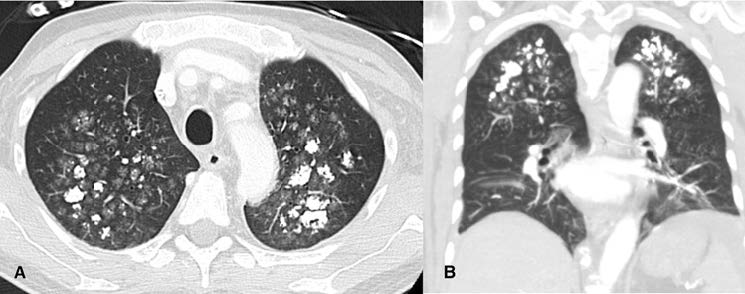

Figure 2: (A) Axial and (B) Coronal chest CT scan showing multiple ground-glass opacities associated with poorly defined centrilobular nodules with coarse areas of calcification, with a symmetrical distribution involving both upper lung lobes.

A 57-year-old man with long-lasting chronic kidney disease due to post-streptococcal glomerulonephritis was referred to our nephrology clinic to perform a second renal transplantation. The patient had a 28-year history of hemodialysis treatment and a first kidney transplant failure. Impaired renal function with normal calcemia, slightly elevated phosphorus, and hyperparathyroidism were observed through laboratory tests. During the previous 3 months, he had a history of non-productive cough with persisting dyspnea. His physical examination was unremarkable. The chest radiograph (Fig.1) revealed numerous small nodular opacities with patchy areas of parenchymal opacification. The nodules were predominant in the upper lung zone and calcification of the nodules was evident. Computed tomography (CT) of the chest showed multiple ground-glass opacities associated with poorly defined centrilobular nodules with ground-glass attenuation and coarse areas of calcification (Fig. 2). There was a symmetrical distribution involving both upper lung lobes and also bronchial calcifications (Fig. 3). There were no visible signs of pleural effusion, pulmonary fibrosis, or lymphadenopathy. Based on these findings and in this setting of end-stage renal disease, the diagnosis of metastatic pulmonary calcification (MPC) was made. Attempt to normalize the patient’s calcium and phosphate biochemistry has been the mainstay of therapy. Following treatment, the patient’s imaging abnormalities have been stable, and he is now waiting for a new transplant match.